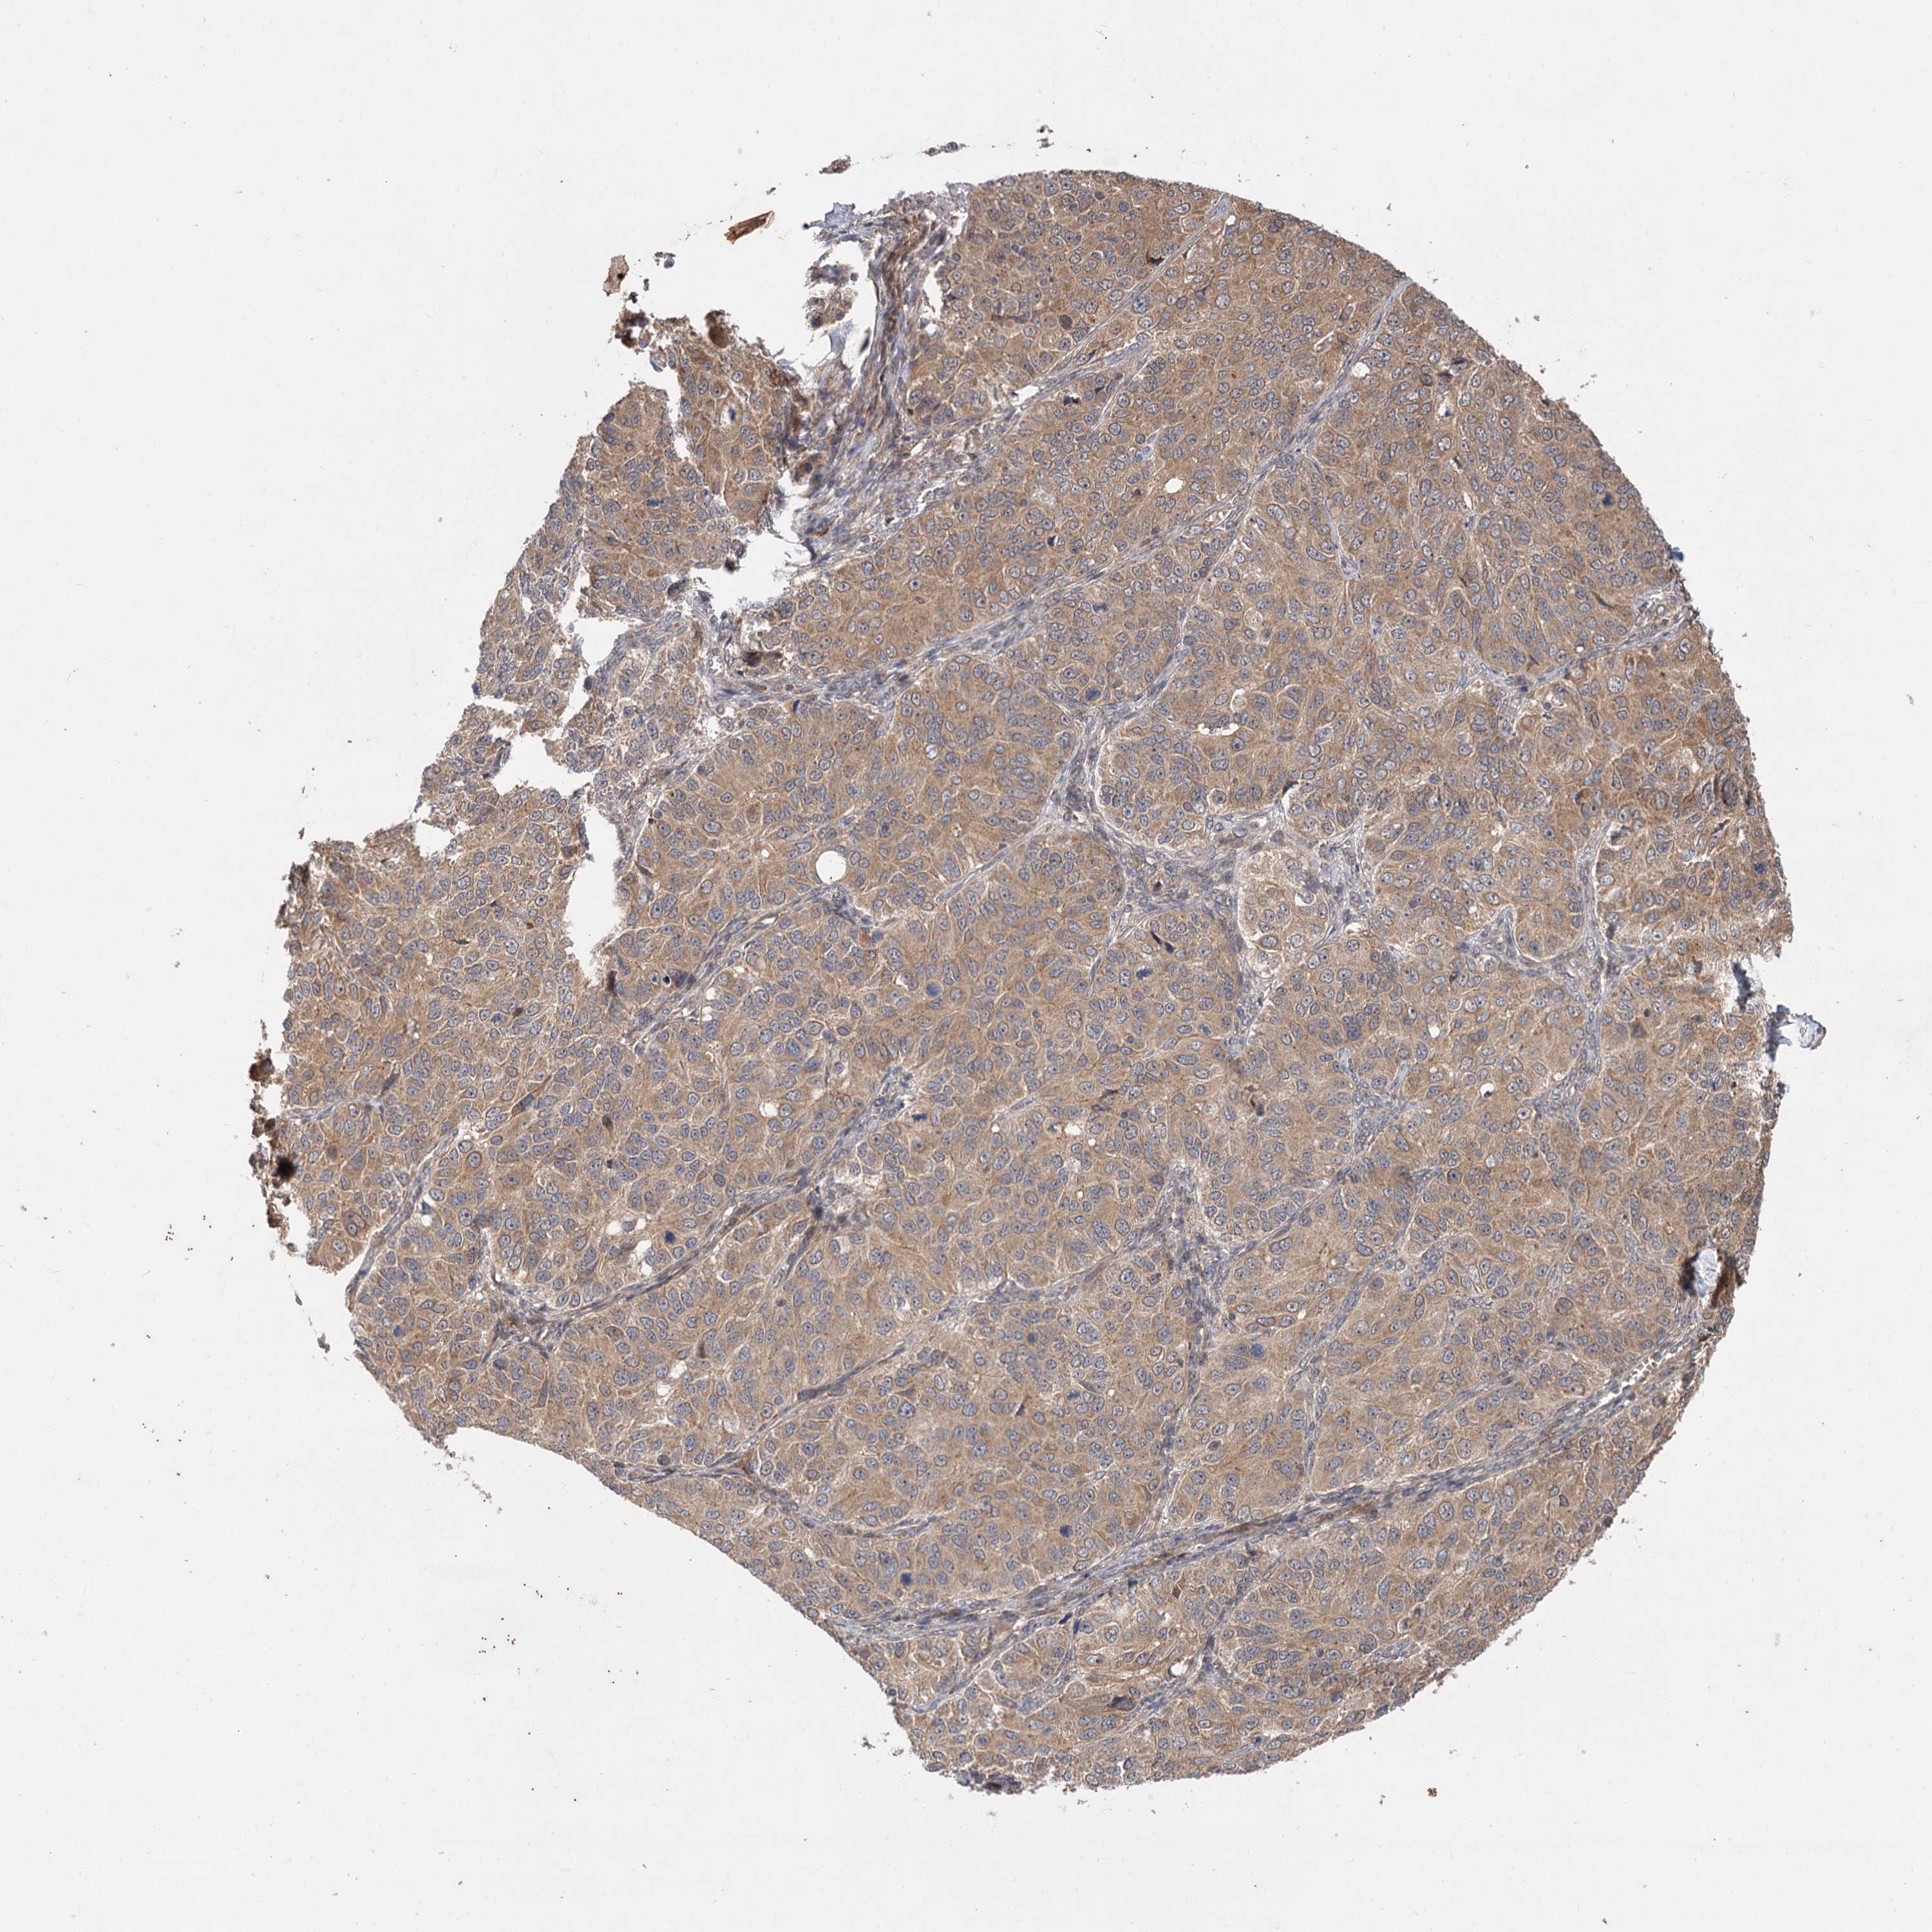

OVARIAN CANCER - Protein expressioni

A mouse-over function shows sample information and annotation data. Click on an image to view it in a full screen mode. Samples can be filtered based on level of antibody staining by selecting one or several of the following categories: high, medium, low and not detected. The assay and annotation is described here.

Note that samples used for immunohistochemistry by the Human Protein Atlas do not correspond to samples in the TCGA dataset.

Antibody stainingi

Antibody staining in the annotated cell types in the current human tissue is reported as not detected, low, medium, or high, based on conventional immunohistochemistry profiling in selected tissues. This score is based on the combination of the staining intensity and fraction of stained cells.

Each image is clickable and will lead to virtual microscopy that enables deeper exploration of all samples and also displays staining intensity scores, fraction scores and subcellular localization as well as patient and tissue information for each sample.

Antibody HPA038850

Antibody HPA038851

Cystadenocarcinoma, serous, NOS

Carcinoma, endometroid

Cystadenocarcinoma, mucinous, NOS

Carcinoma, NOS